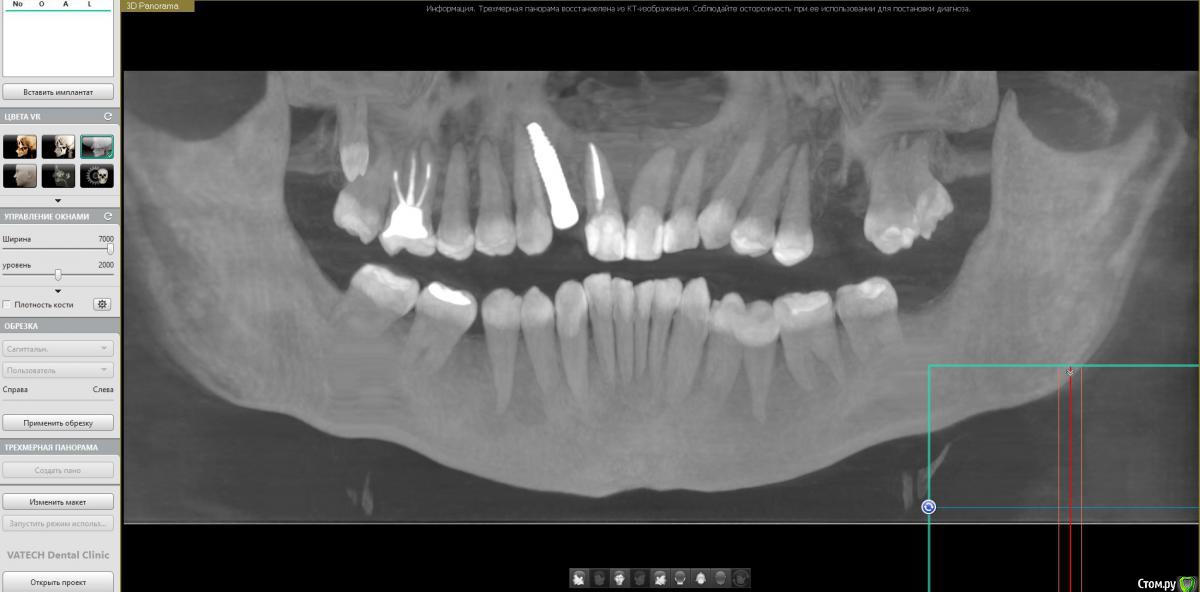

stanx11 Опубликовано 29 августа, 2020 Поделиться Опубликовано 29 августа, 2020 (изменено) Добрый день. Уже не знаю куда обращаться. Случилась такая ситуация. 2 месяца назад удалили верхнюю двойку и сразу поставили имплант. Все вроде бы прошло хорошо, но спустя пару дней разболелась верхняя шестерка. На ней была киста, сам зуб уже был старый и плохо пролеченный изначально (20 лет назад). поэтому его пришлось удалить. В момент удаления. как мне показалось был хруст в области передних верхних зубов и в этот же день стали болеть 2 верхних зуба (оставшаяся двойка и единица рядом с ней). Хирург говорит, что не возможно чтобы от нажатия на корень шестерки повредились передние зубы. Но они же болят и проблема в том, что помимо верхних со временем стали болеть еще и нижние тоже передние зубы. Обошел кучу терапевтов\хирургов\ортодонтов и никто не может сказать ничего конкретного. Все говорят. что зубы хорошие, нет ни кариеса, ни реакции на холодное\горячее и что показаний к депульпированию нет. Но тем не менее болят зубы почти месяц, причем только передние (верхние и нижние). Думал, что это из изменившегося прикуса, но уже 3 недели ношу и сплю в каппе, все равно не помогает. Наблюдаюсь у Невролога, принимаю карбамазепин. Но тоже эффекта ноль. Может ли быть боль невралгическая, если болят только передние зубы? прикрепляю снимок, если есть неравнодушные-скину полное КТ. Уже не знаю, что делать. и ссылка на КТ https://yadi.sk/d/MCgAGnmGOIAHQQ Изменено 29 августа, 2020 пользователем stanx11 Ссылка на комментарий

stanx11 Опубликовано 30 августа, 2020 Автор Поделиться Опубликовано 30 августа, 2020 (изменено) Болит постояно? Пятёрка возле удалённого холод чувствует?.нет, вообще никакие зубы не чувствуют ничего, ни холод-ни тепло. Двойка может только на постукивания реагировать сильнее чем остальные и все...Да, полит почти постоянно, просто в разные моменты времени что-то больше, что-то меньше. Но болят только передние зубы, причем даже мертвая единица. Был пульпит в восьмерке (на снимке он остался), его удалили неделю назад, но ничего не изменилось. Изменено 30 августа, 2020 пользователем stanx11 Ссылка на комментарий